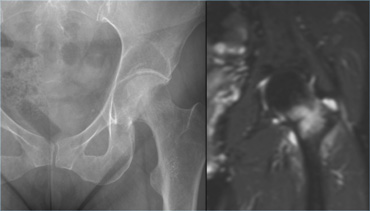

Stress fracture of the femoral neck located on the compression side. Stress fracture of the femoral neck located on the compression side.

There are two types of stress fractures of the femoral neck:

1. Compression fracture. These are located on the inner side of the femoral neck.

They have a low risk of complicated healing with conservative therapy, because the fracture parts are pressed together.

2. Tension fracture. These are located on the outer side of the femoral neck.

They have a high risk of complicated healing due to tension exerted on the fracture elements. These fractures are at risk for complete fracture and avascular necrosis.

If conservative therapy fails, open reduction and internal fixation is recommended.

On the left we see a compression fracture of the femoral neck.

The radiograph is normal, but MR depicts the fracture and bone marrow edema (i.e.grade 4).